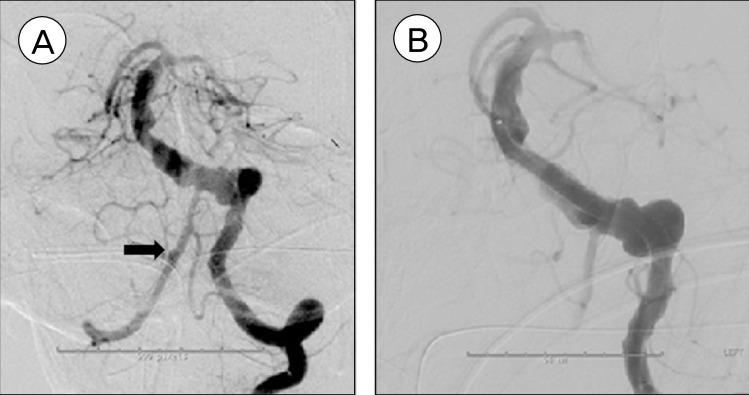

Treatment options of ruptured vertebrobasilar fusiform aneurysms (VFA) are limited and often carry significant mortality and morbidity. We report the use of Pipeline Embolization Device (PED) to successfully treat a patient with a ruptured vertebrobasilar fusiform aneurysm (VFA) who presented with subarachnoid hemorrhage (SAH). A 73 year-old man with a history of cardiac stent placement seven days earlier presented with Hunt-Hess II SAH. He was taking aspirin and clopidogrel. Computed tomography angiogram revealed a large vertebrobasilar fusiform aneurysm. Microsurgical treatment options are technically challenging and carry high risk. He underwent endovascular treatment of the ruptured VFA using overlapping PEDs. Five PEDs were placed in a telescoping fashion to reconstruct the affected portions of the left vertebral and basilar arteries. An additional 2-mm blister aneurysm in the right vertebral artery was also discovered during the conventional cerebral angiography and was treated with one additional PED. The patient remained neurologically intact after the procedure. He was continued on aspirin and clopidogrel. Follow-up magnetic resonance imaging at three months demonstrated patency of the stents without any evidence of ischemic change. Follow-up conventional cerebral angiogram at six months demonstrated thrombosis of the VFA and reconstruction of the vertebrobasilar system. The patient remained clinically well. An endovascular approach using PEDs can be a safe and effective treatment option for ruptured VFA in selected cases.

破裂性椎基底动脉梭形动脉瘤(VFA)的治疗选择有限,且往往伴有显著的死亡率和发病率。我们报告了使用Pipeline栓塞装置(PED)成功治疗一名患有破裂性椎基底动脉梭形动脉瘤(VFA)并伴有蛛网膜下腔出血(SAH)的患者。一名73岁男性,7天前有心脏支架置入史,现出现Hunt-Hess II级SAH。他正在服用阿司匹林和氯吡格雷。计算机断层血管造影显示一个大型椎基底动脉梭形动脉瘤。显微外科治疗选择在技术上具有挑战性且风险很高。他接受了使用重叠PED对破裂的VFA进行血管内治疗。以套叠方式放置了5个PED,以重建左椎动脉和基底动脉的受累部分。在常规脑血管造影期间还发现右侧椎动脉有一个额外的2毫米泡状动脉瘤,并用另外一个PED进行了治疗。术后患者神经功能保持完好。继续给予他阿司匹林和氯吡格雷。3个月后的随访磁共振成像显示支架通畅,没有任何缺血改变的迹象。6个月后的随访常规脑血管造影显示VFA血栓形成以及椎基底系统重建。患者临床状况良好。在某些情况下,使用PED的血管内治疗方法对于破裂性VFA可能是一种安全有效的治疗选择。